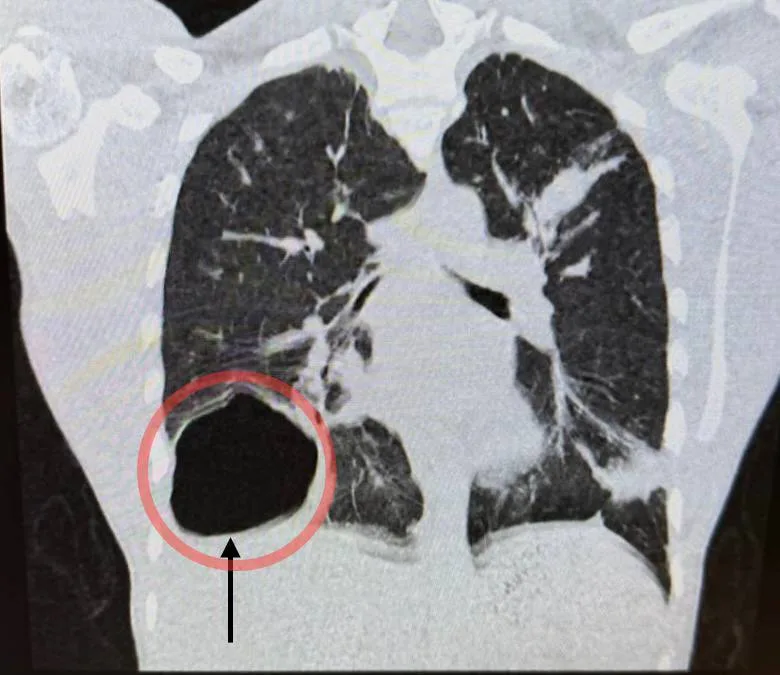

Проведенная диагностика выявила крупную паразитарную кисту правого легкого. Ее размер был сопоставим с размером головы новорожденного ребенка. Киста образовалась из-за попадания в организм гельминта - эхинококка.

«После подтверждения диагноза с помощью лабораторного контроля и компьютерной томографии мы приняли решение о проведении операции. В нашем отделении накоплен большой опыт хирургического лечения данной патологии малоинвазивными методами через несколько проколов. Такая щадящая операция сильно сокращает травматичность вмешательства и сроки реабилитации. В данном случае мы избежали широкого разреза. Операция прошла успешно, послеоперационный период протекал без особенностей», - сказал заведующий отделением детской хирургии Владимир Трунов.